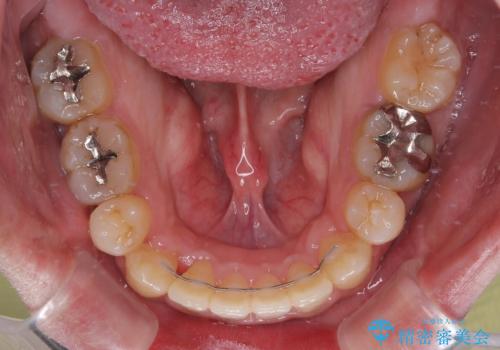

- 口が閉じられないとのことで来院された患者様です。

顎先に力を入れないと唇が閉じきれない口元であったので、上下左右の第一小臼歯4本を抜歯して、ワイヤー装置にて矯正治療を行うこととしました。

2年から2年半の治療期間を想定しており、予定通りの期間で無事に終了することができました。

唇や顎先に力を入れないなくてもスムーズに唇を閉じることができるようになりました。